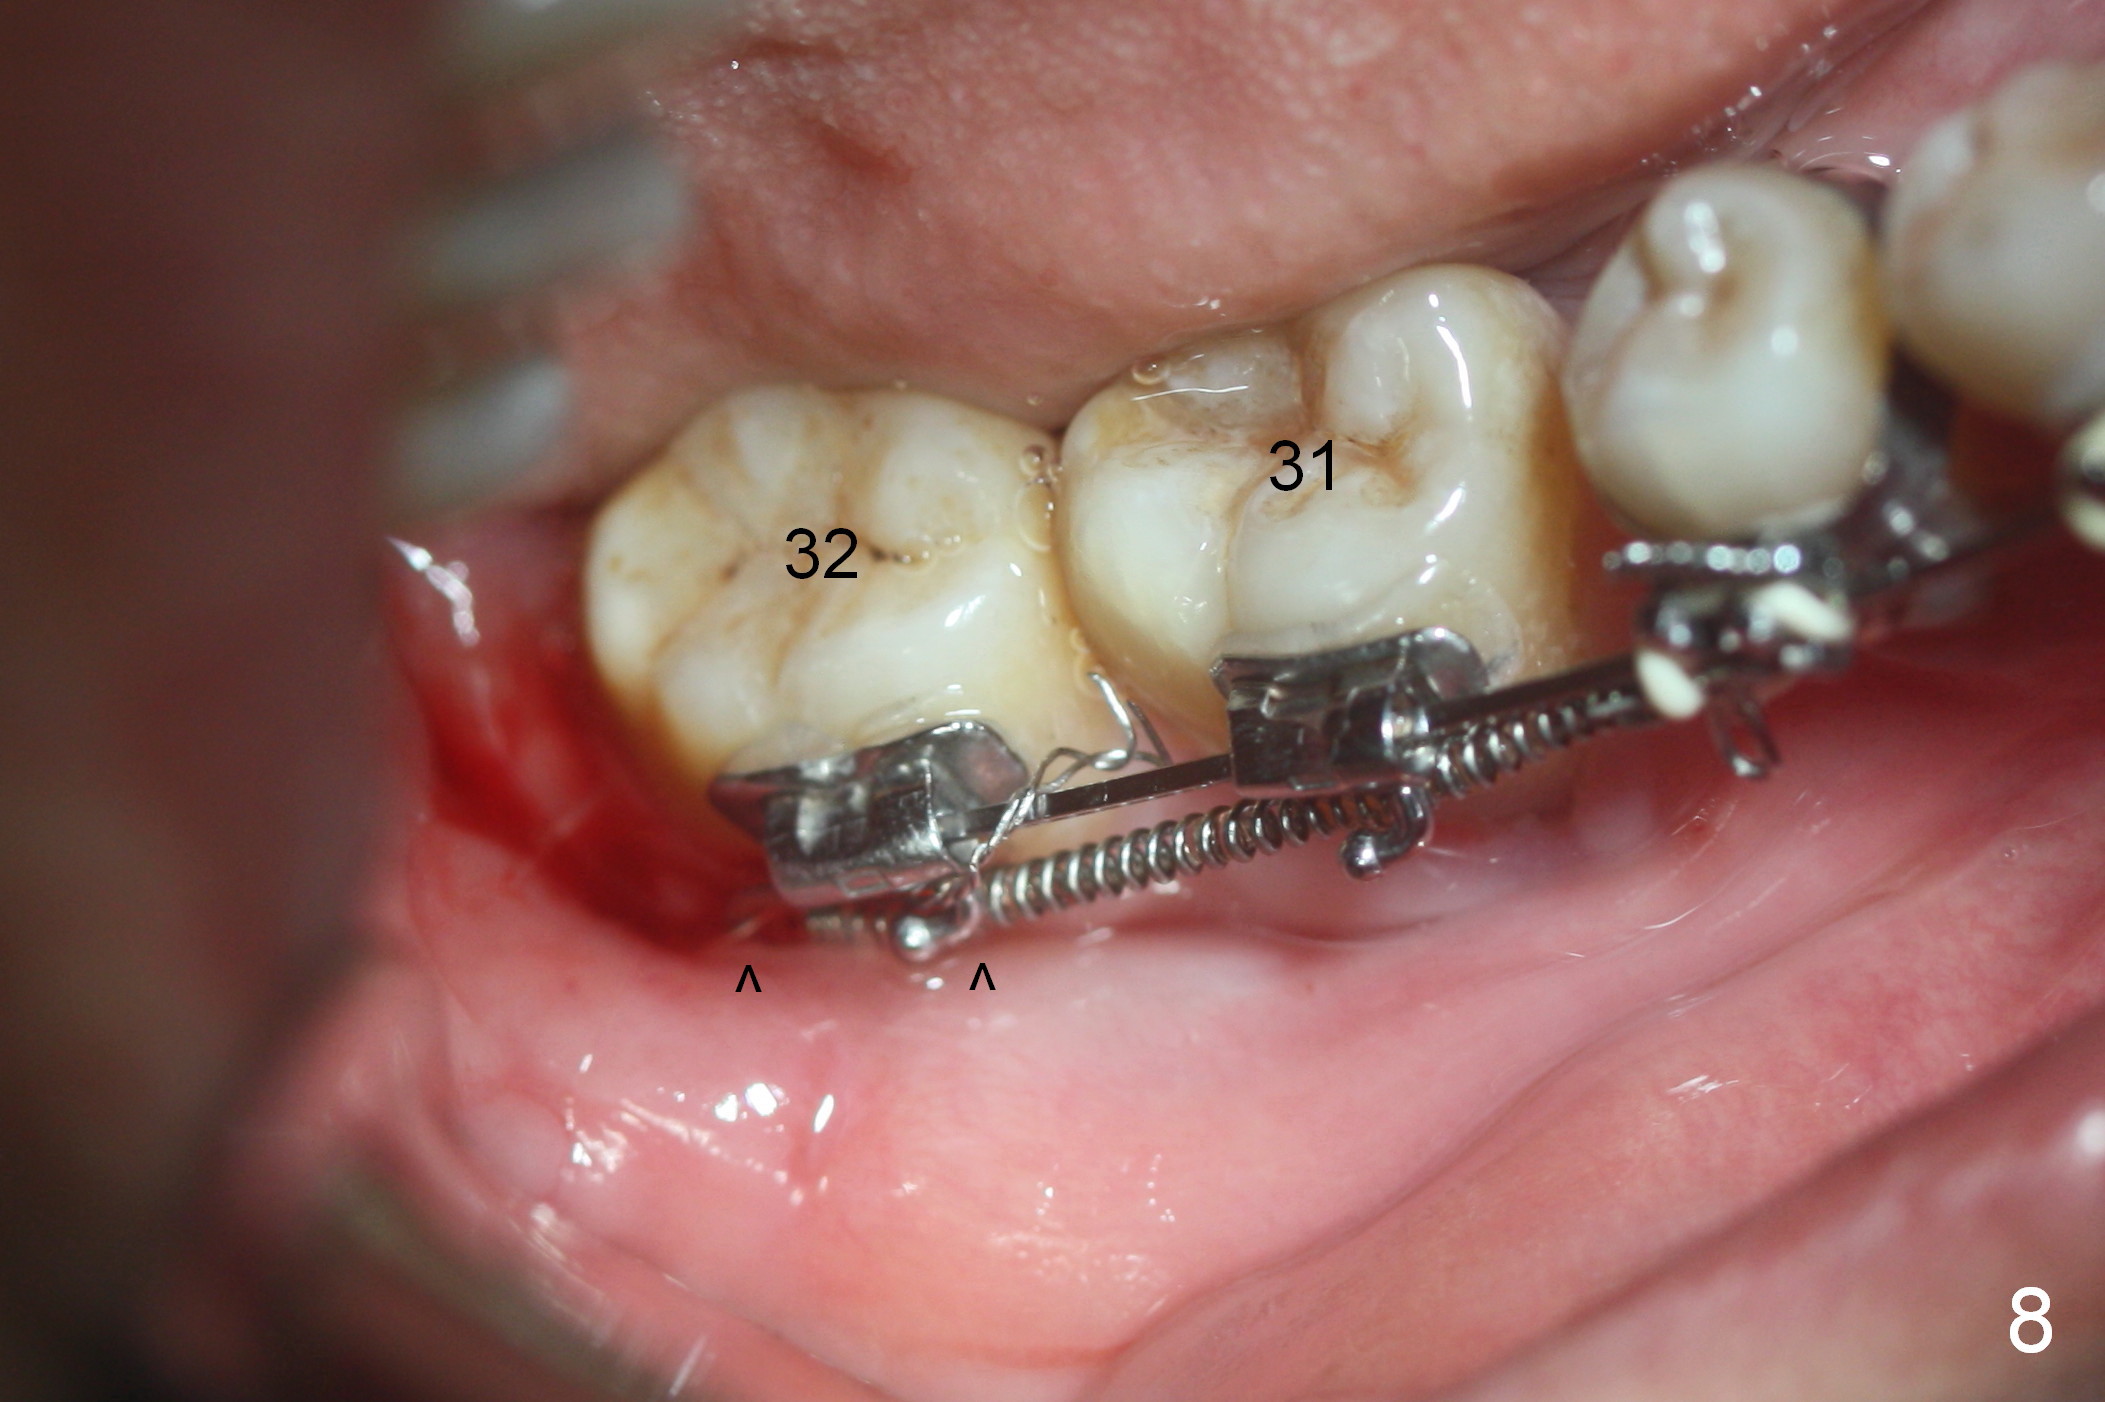

A 47-year-old lady has lost the lower right 1st molar for long time; with reduction of the buccolingual width (Fig.1) and mesiodistal width (Fig.2,3). With regional orthodontic appliance (Fig.4) for 3 months, the tooth #29 has started being distalized (Fig.5). One month and a half later, the tooth #26 starts to shift labially. Power chains and then closed coil spring are placed between #29 and 32. #29 distalization is slow (Fig.7) with closure of the diastema between #31 and 32 (Fig.8, as compared to Fig.1,3). Seven months post banding, a 10 mm miniimplant is placed distobuccal to the tooth #32 (Fig.6); the same 12-mm closed spring is stretched distal by ~ 6 mm (Fig.8 between arrowheads). Two months later, #29 is more distalized (Fig.9 tilted) with bone deposit mesially (*) and coronally (^). A .018' stainless steel wire is installed with an open coil spring placed between #28 and 29 (Fig.10 (^),11). Note #29 rotation (Fig.11). To solve the tilting, a power hook (Fig.12 black) will be clamped to a .016x.016 wire (red), while the closed spring is lowered and attached to the power hook (Fig.12 white). Take photos after removing the existing wire occlusally to show the alveolar width change. When the wire is placed, make sure that the distal wings of #29 bracket is fully engaged to reduce the tooth rotation. Make occlusal adjustment on #31 and 32 to reduce anterior open bite.